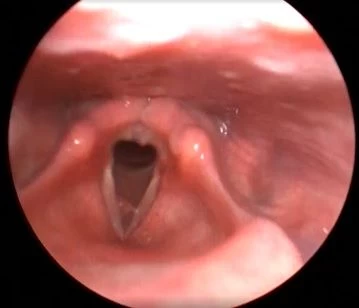

Клинический случай №2. Хирургическое лечение двустороннего паралича гортани с применением лазера 445 нм.

В нашей клинике лечение этих пациентов проводится по методу, разработанному Кривопаловым А. А., который хорошо себя зарекомендовал.

После операции проявления воспаления минимальны. Через месяц после вмешательства пациенты готовы перейти к следующему этапу восстановления – занятиям с логопедом.

Рис 2А. Двусторонний паралич гортани. До операции.

Рис 2Б. Двусторонний паралич гортани. На 7 сутки после операции.

Рис 2В. Двусторонний паралич гортани. На 1 месяц после операции.